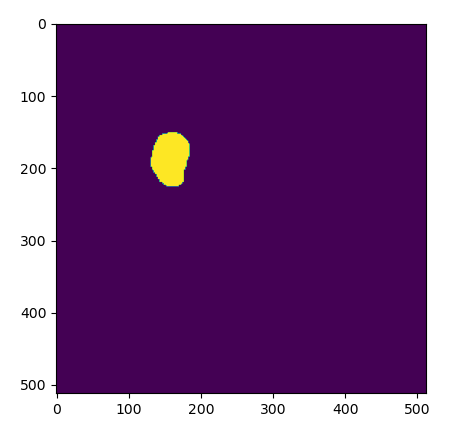

![[10] DICOM RT structure, plot contours - YouTube](https://i.ytimg.com/vi/tubB3k6yE-o/maxresdefault.jpg)